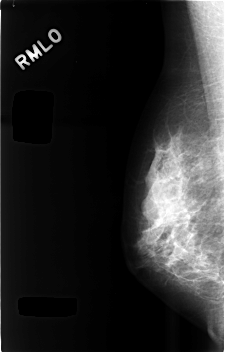

C_0494_1.RIGHT_MLO

RIGHT_MLO LINES 4568 PIXELS_PER_LINE 2920 BITS_PER_PIXEL 12 RESOLUTION 50 NON_OVERLAY